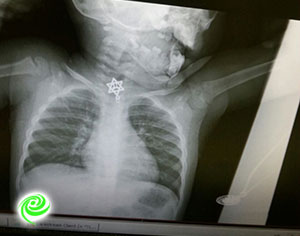

אומרים שעל ילדים קטנים צריך אלף עיניים ואפילו עיניים בגב? הנה דוגמא למקרה שתודה לאל הסתיים בשלום, ילדה בת שנה וחצי בלעה תליון של מגן דוד , הילדה הפקחית מיד באה לאמה והתלוננה על כאבי גרון, ההורים הלחוצים מיד הבינו ופינו את התינוקת לקפלן, שם נותחה הילדה והתליון הוצא בשלום. המשפחה מבקשת להודות לצוות המסור בבית חולים קפלן. סוף טוב הכל טוב.